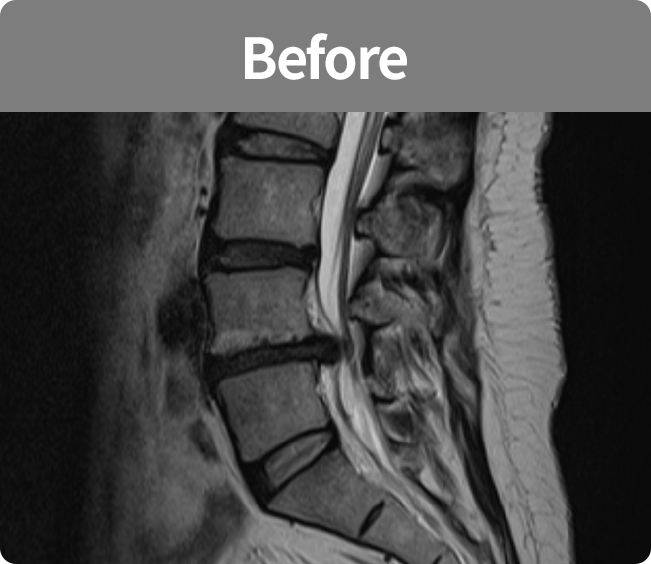

척추유합술

미세현미경을 통해 손상된 뼈와 인대조직을 제거하고 디스크의 역할을 해줄 인조 케이지를 삽입해

불안정한 척추체를 나사못으로 고정하는 수술 (척추 전방 골유합술, 척추 후방골유합술)